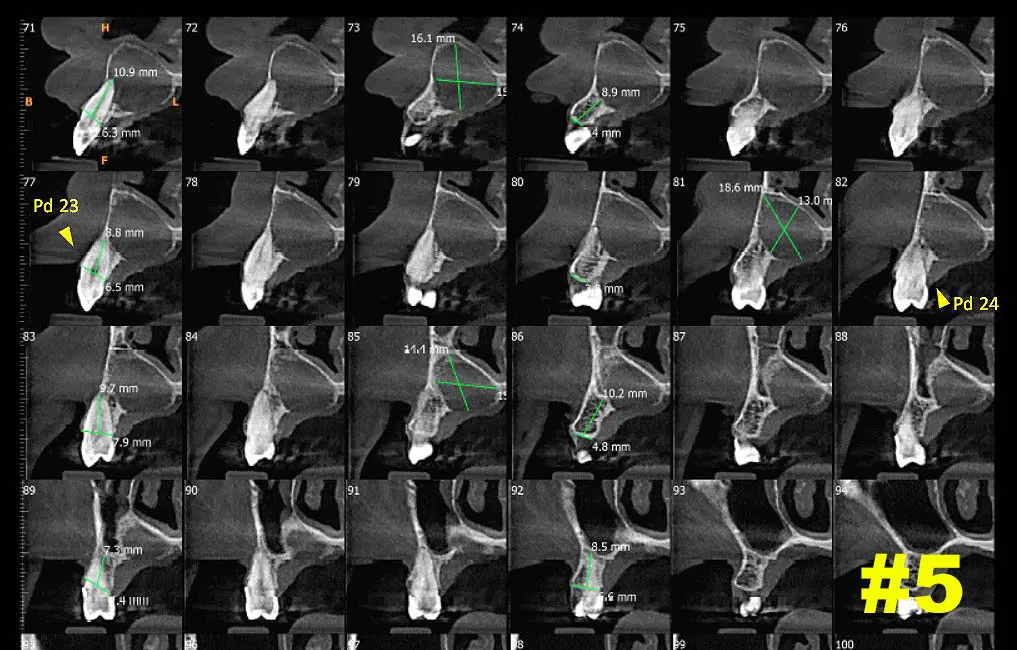

​Dicha lesión vemos que provoca expansión y abombamiento hacia piso de fosa nasal izquierda como también hacia cara palatina. Ver Imagen 2 Y 3. También se puede ver en una navegación  en cortes cada 1mm como se comporta la lesión - ver imágenes 4 y 5 (cortes transaxiales)